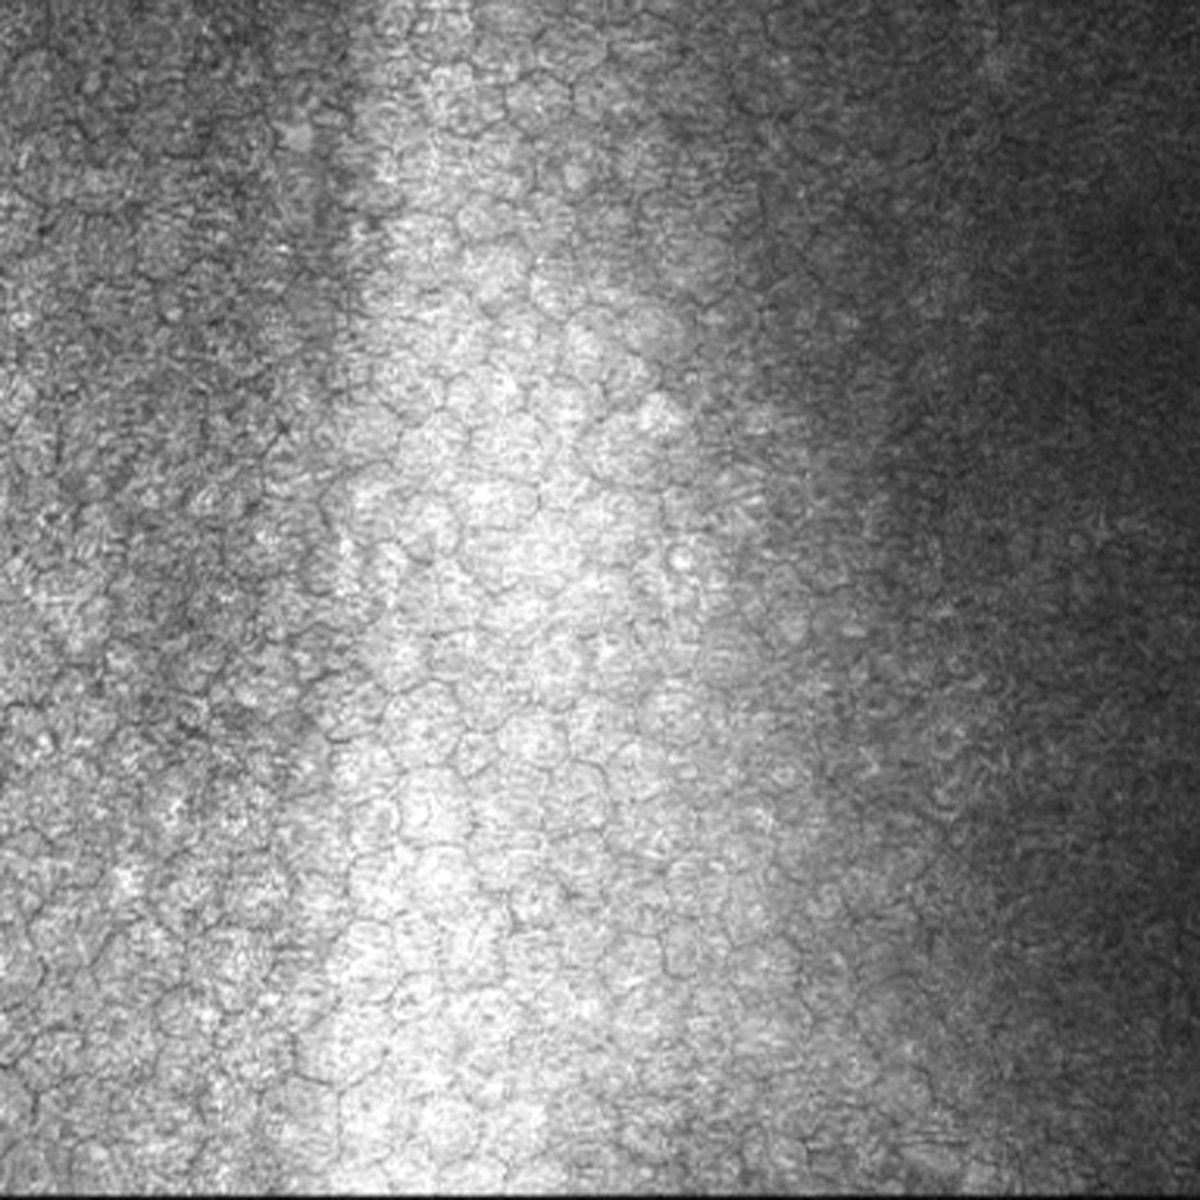

Figure 5 of Vincent, Mol Vis 2013; 19:852-860.

Figure 5. In vivo confocal microscopy in this patient with keratoconus, heterozygous for the visual system homeobox 1 p.His244Arg variant shows a healthy endothelium. (Scale bar=100 μm)